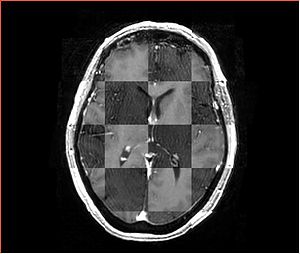

• Checkerboard appearance of unregistered images for the representative data of interest

• Case01